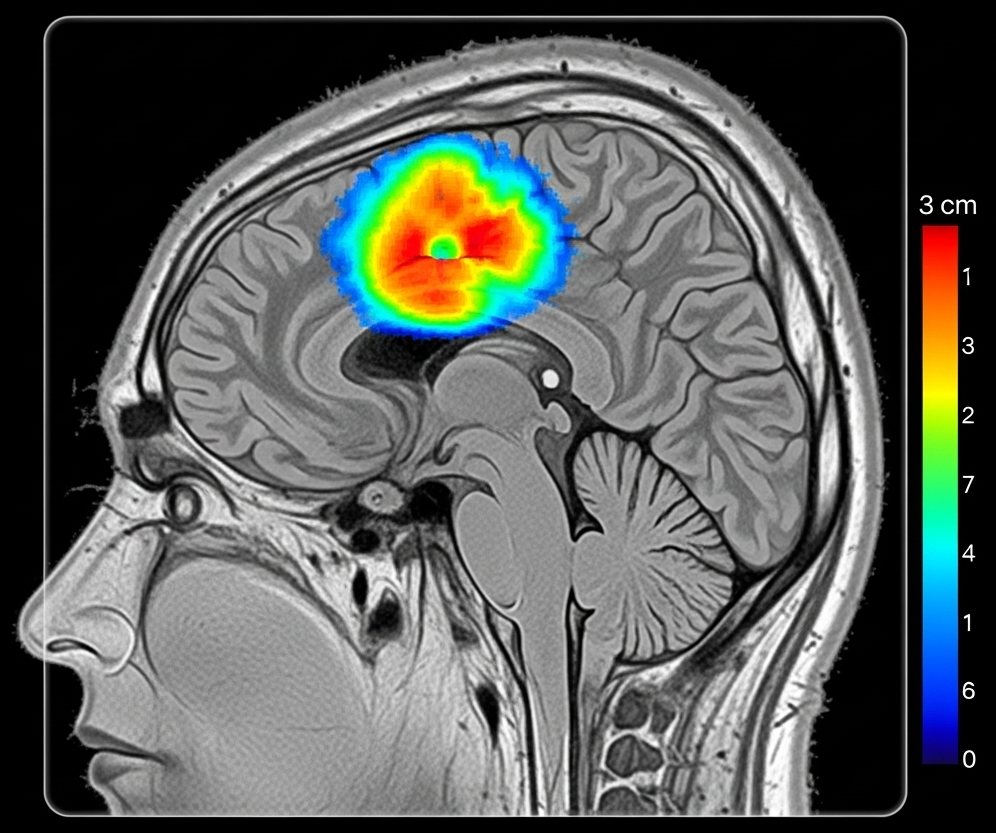

Gradient-based methods represent the most intuitive approach to understanding neural network decisions. Techniques like Gradient-weighted Class Activation Mapping (Grad-CAM) work by examining how changes in input pixels affect the final prediction. Imagine highlighting exactly which pixels in a brain MRI contributed most strongly to a tumor classification—that’s essentially what Grad-CAM accomplishes. The method backpropagates gradients from the final prediction to generate heatmaps showing pixel-level importance.

Consider glioblastoma detection, where explainable AI has achieved remarkable clinical integration. Modern systems don’t just identify suspicious lesions; they provide detailed reasoning that aligns with established radiological criteria. A typical explanation might highlight regions of contrast enhancement, areas of restricted diffusion, and patterns of perilesional edema—precisely the features a neuroradiologist would examine.

A groundbreaking example comes from federated learning implementations for brain tumor classification. The collaborative model developed by Mastoi et al. demonstrates how XAI can maintain transparency even when training across multiple institutions. Their system uses attention mechanisms to highlight tumor boundaries while providing confidence scores for different anatomical regions. When classifying a meningioma versus glioma, the system might show high attention to the tumor-brain interface (characteristic of meningiomas) while providing lower confidence scores for regions with imaging artifacts.

Multi-parametric MRI analysis represents another frontier where explainability proves crucial. Brain tumors require assessment across multiple imaging sequences—T1-weighted, T2-weighted, FLAIR, and diffusion-weighted imaging. Explainable AI systems can integrate findings across these modalities while showing which sequences contribute most strongly to specific diagnostic conclusions. This multi-modal reasoning mirrors the complex thought processes of expert neuroradiologists.